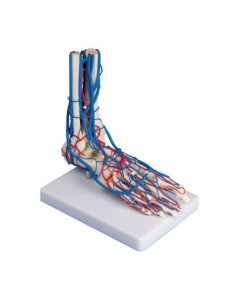

Esplora la nostra collezione dei migliori modelli anatomici degli arti superiori ed inferiori

La nostra esclusiva selezione di modelli anatomici delle estremità, meticolosamente prodotti dai leader del settore 3B Scientific ed Erler Zimmer, offre una rappresentazione fedele e dettagliata delle complesse strutture di mani e piedi. Questi modelli sono fondamentali per chiunque desideri esplorare l’anatomia delle estremità con una precisione senza pari, rendendoli strumenti didattici ideali per l’educazione e la pratica in ortopedia, fisioterapia e medicina dello sport.

Ortopedici, fisioterapisti, studenti di scienze della salute e istituti educativi si affidano ai nostri modelli per le loro esigenze educative e professionali, utilizzandoli per dimostrazioni pratiche e per migliorare la comprensione della meccanica e della funzione delle estremità umane.